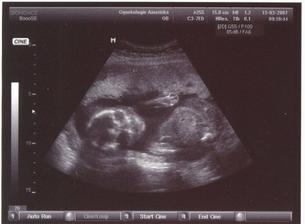

SRPŇÁTKA 2007 - fotky UTZ

album věnované mimískům, které se narodí v srpnu 2007 a jejich maminkám ze "Společného termínu SRPEN"